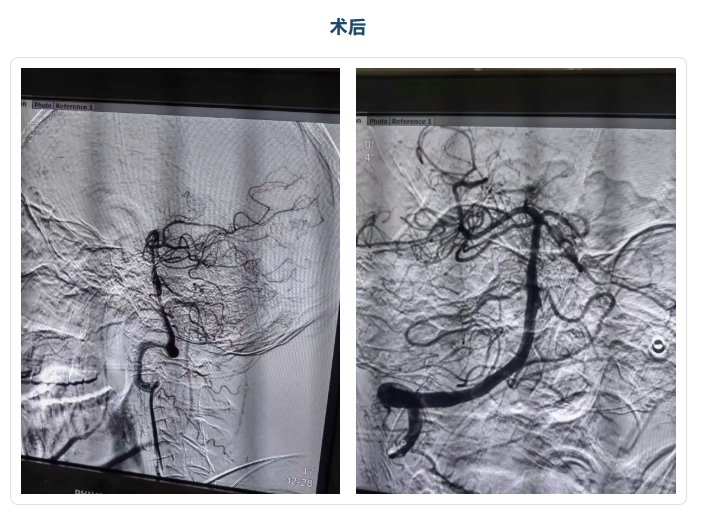

术中造影清晰提示:患者基底动脉完全闭塞,这正是导致他昏迷的根本原因。面对血管条件差的难题,手术团队凭借丰富的临床经验和精湛的操作技巧,采用长鞘结合远端通路导管,通过同轴技术建立稳定通路,借助中间导管高到位,精准将器械送达血栓所在位置,成功攻克了器械到位难的难关。随后,团队有条不紊地继续操作:同轴引入132cm Catalyst6一次性颅内抽吸导管至右侧椎动脉V3段,再用200cm Synchro2微导丝引导微导管Trevo Pro18超选至基底动脉末端,微导管造影证实进入真腔后,引入Trevo XP 4*20取栓支架释放。

造影显示,远端血管开始显影,但基底动脉中段仍有大量血栓残留——心源性血栓的坚韧质地,让取栓过程格外艰难。针对这一问题,手术团队采用Solumbra技术(支架取栓+负压抽吸联合技术),将支架留置5分钟后,在负压抽吸下缓慢回收取栓支架,大量血栓被成功取出,血管局部实现再通。但为了确保血流完全通畅,降低后续复发及远端栓塞风险,团队再次重复支架辅助+负压抽吸取栓操作,又取出大量残留血栓,成功破解了血栓负荷大、易逃逸的难题。

当再次造影时,所有人都松了一口气——远端血管完全再通,血流恢复正常,这意味着手术取得了关键胜利,也成功规避了再灌注损伤的风险!患者在麻醉复苏后,意识就有了明显好转。经过10天的住院综合治疗,老人的症状持续好转,失语情况逐渐改善,肢体力量也在慢慢恢复。为了进一步促进神经功能康复,让老人能更好地回归生活,医院为其安排转至康复科,接受专业的康复训练。目前患者已康复出院,整体恢复情况良好。